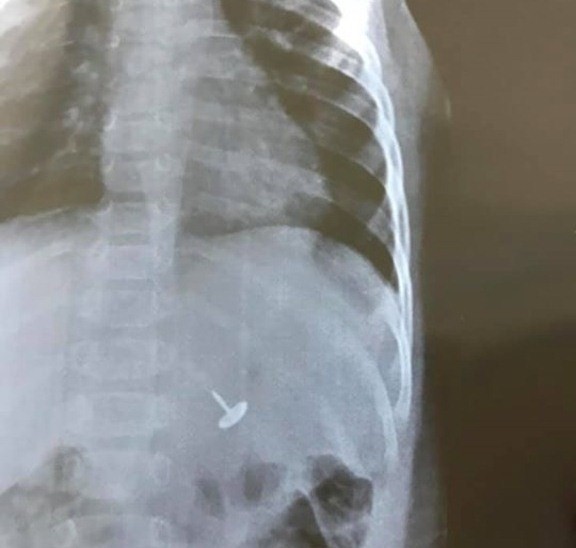

Gia đình bệnh nhi cho biết, cháu N tự nuốt phải dị vật kim khí trong lúc chơi. Thấy cháu quấy khóc, gia đình đã nhanh chóng đưa cháu đến Trung tâm Y tế Tiên Yên. Kết quả chụp X-Quang cho thấy hình ảnh dị vật là chiếc đinh vít nhọn nằm ở phình vị của dạ dày.

Hình ảnh chiếc đinh vít qua phim chụp